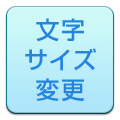

画像のような装置を腕や尾にピタリと巻き付けます。測定中は人間の血圧計のように巻き付けた帯が一度最大に膨らみ、その後シューッと空気が抜けてしぼみます。これで測定は完了です。

いたって簡単な検査なのですが、測定中に動いてしまうと正確な値が出ませんので、いかにして動物が落ち着いた状態でいてくれるか?がポイントになります。